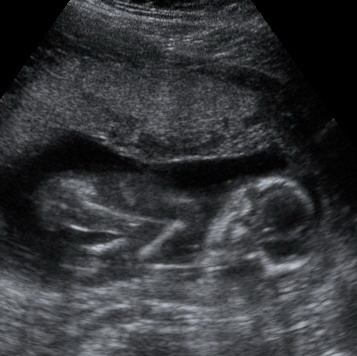

Ha esetleg nem látnátok: a lábai az égnek állnak, és közte a fütykös kb. akkora, mint a nyíl. (mármint golyszli és rajta a fütykös :wink: :lol: )

KépKép